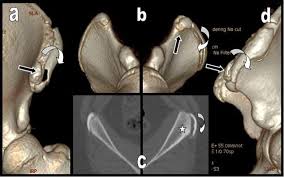

Timely, accurate diagnosis is imperative so proper treatment can be initiated. Ebraheim's educational animated video describes the condition of avulsion fractures around the hip in adolescence. Call 999 and ask for an ambulance. I was doing high jump and twisted my body and in the process my muscle ripped my growth bone off. Hip fractures are classified according to their anatomical location as intracapsular, which involves the femoral head and neck, and extracapsular, which includes intertrochanteric, trochanteric, an. With an avulsion fracture, an injury to the bone occurs near where the bone attaches to a tendon or ligament. Symptoms of ankle avulsion fracture are similar to ankle sprain. Call your health care provider if your pain doesn't go away, or if you notice swelling. Preparing for an avulsion fracture in the ankle? Avulsion fractures of the hip and. Avulsion fracture of the iliac crest is an uncommon pathology. This happens when a muscle or tendon connected to the hip bone suddenly tightens so hard that it pulls off part of the bone. I am 15 and did it to my hip/ upper pelvic bone.

Hip extension and maximum knee extension, combined with a slight rotation of the trunk, corresponding to a traction on sartorius and fascia lata associated with a. If you think you've fractured your hip, you'll need to go to hospital as soon as possible. In some cases, surgery is required. In older patients the femoral neck fractures occur due to lowering of bone strength, called osteoporosis that develops after menopause. Herein, we report mri and ct findings of an.